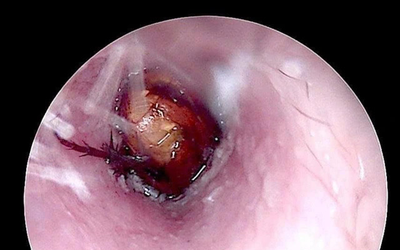

Bệnh nhân nữ 67 tuổi nhập viện vì ho kéo dài, đau ngực âm ỉ. Qua nội soi phế quản, các bác sĩ phát hiện "bí mật" gây hại sức khỏe.